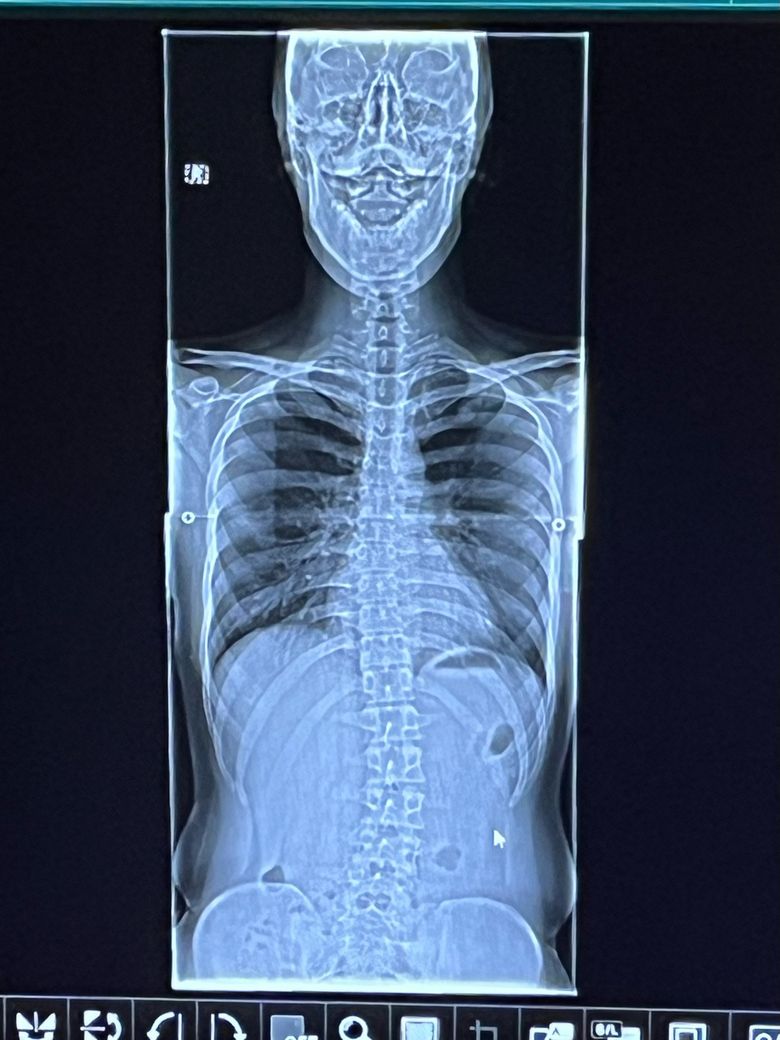

x-ray로 보았을 때는 척추측만증과 골반 틀어짐 등 신체 불균형이 있는 것으로 보입니다.

우선 엑스레이상 뼈가 많이 틀어진 측만증을 의심하기보다는 마일드 수준으로 보여집니다.

약간의 측만증은 있어보입니다